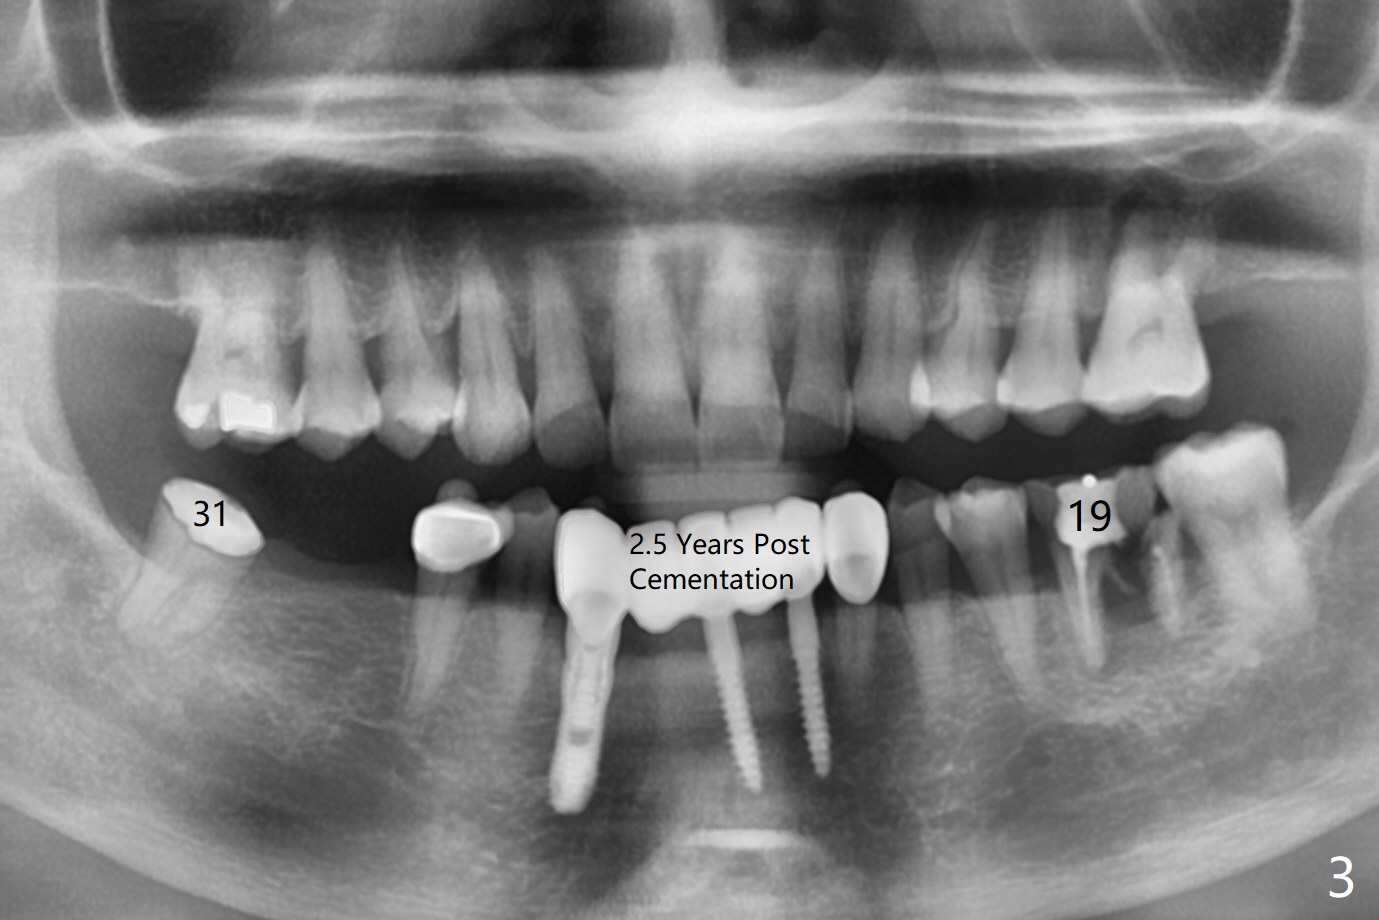

A 61-year-old woman with history of bruxism returns to clinic with chief complaint "I cannot chew bottom right. Top left has had pain and swelling before". Exam shows loose FPD at #31 (Fig.1) and necrosis of #14 (Fig.2). When the FPD is sectioned, the tooth #31 is found to have subgingival caries, filled with IRM (Fig.3). CT shows large PARL around MB and P roots of the tooth #14 (Fig.4), the fractured distal root of the tooth #19 with the low buccal plate (Fig.5) and a 5x10 mm implant being able to be placed at #30 (Fig.6). The crestal cortex (Fig.7 arrowheads) is thin in the edentulous area for several decades. The bone density is low (Fig.8, underprep). To place an implant over the pointed ridge, it should be trimmed prior to osteotomy (Fig.9). The bone loss associated with the fractured distal root is severe at #19 (Fig.10). After removal of the mesial root (Fig.11: 1), perform distal socket shield (2).